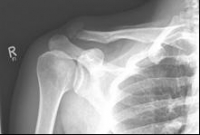

Picture 1: Displaced fracture of the left collarbone before surgery.